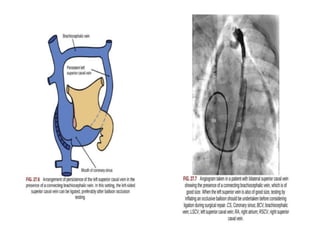

What if the brachiocephalic anastomosis fails?

Moore & Persaud

BILATERAL SUPERIOR VENAE CAVA

COURSE OF LSVC

follows the course of the embryonic left cranial cardinal vein. It enters the pericardial cavity

to the left of the left upper pulmonary veins, and runs posterior to the dome of the left

atrium, having the mouth of the left atrial appendage to its left side. As it passes inferiorly,

it accepts the hemiazygos vein and descends medially into the inferior atrioventricular

groove. In nine-tenths of cases, the persistent left superior caval vein drains into the

morphologically right atrium through an enlarged mouth of

the coronary sinus

• THE SIZE OF THE LSVC VARIES

• LEFT INNOMINATE VEIN MAY BE PRESENT IN

60%

• THE LSVC STARTS AT THE JUNCTION OF THE LEFT

JUGULAR AND LEFT SUBCLAVIAN VEINS

• JOINS THE CORONARY SINUS IN THE POSTERIOR

LEFT AV GROOVE